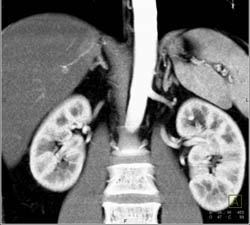

Duplicated Collecting System on the Left and Right- See Dilated Calyces on Left